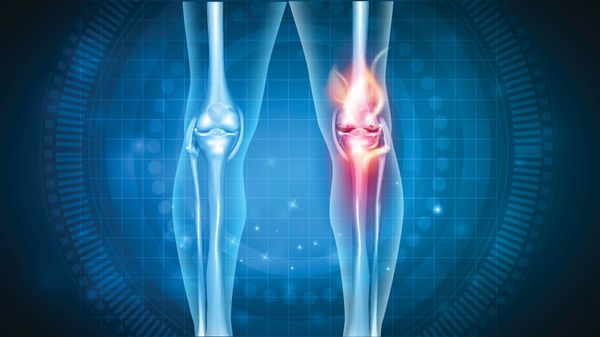

Gonarthrose des Kniegelenks

Das Knie besteht aus mehr als Oberschenkelknochen (Femur) plus Schienbeinknochen (Tibia): Meniskus, Kniescheibe (Patella) sowie ausgeprägte Sehnen und Bänder verkomplizieren den Aufbau. Verschleißerscheinungen treten in den verschiedenen Kompartimenten auf. Femoropatellarathrosen zwischen Oberschenkelknochen und Kniescheibe behindern das Treppensteigen. Mediale und laterale Femorotibialarthrosen auf Innen- und Außenseite von Oberschenkel und Schienbein schmerzen bei Beugen oder Strecken.Typisch für Gonarthrosen ist ein Krankheitsbeginn im fünften Lebensjahrzehnt. Je weiter die Arthrose fortschreitet, desto häufiger breitet sie sich auf das gesamte Knie aus (panartikuläre Gonarthrose).